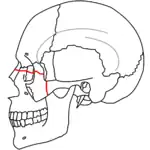

At the beginning of the 20th century, René Le Fort mapped typical locations for facial fractures; these are now known as Le Fort I, II, and III fractures (right).[7] Le Fort I fractures, also called Guérin or horizontal maxillary fractures,[14] involve the maxilla, separating it from the palate.[15] Le Fort II fractures, also called pyramidal fractures of the maxilla,[16] cross the nasal bones and the orbital rim.[15] Le Fort III fractures, also called craniofacial disjunction and transverse facial fractures,[17] cross the front of the maxilla and involve the lacrimal bone, the lamina papyracea, and the orbital floor, and often involve the ethmoid bone,[15] are the most serious.[18] Le Fort fractures, which account for 10–20% of facial fractures, are often associated with other serious injuries.[15] Le Fort made his classifications based on work with cadaver skulls, and the classification system has been criticized as imprecise and simplistic since most midface fractures involve a combination of Le Fort fractures.[15] Although most facial fractures do not follow the patterns described by Le Fort precisely, the system is still used to categorize injuries.[5]

| Le Fort II fractures | |